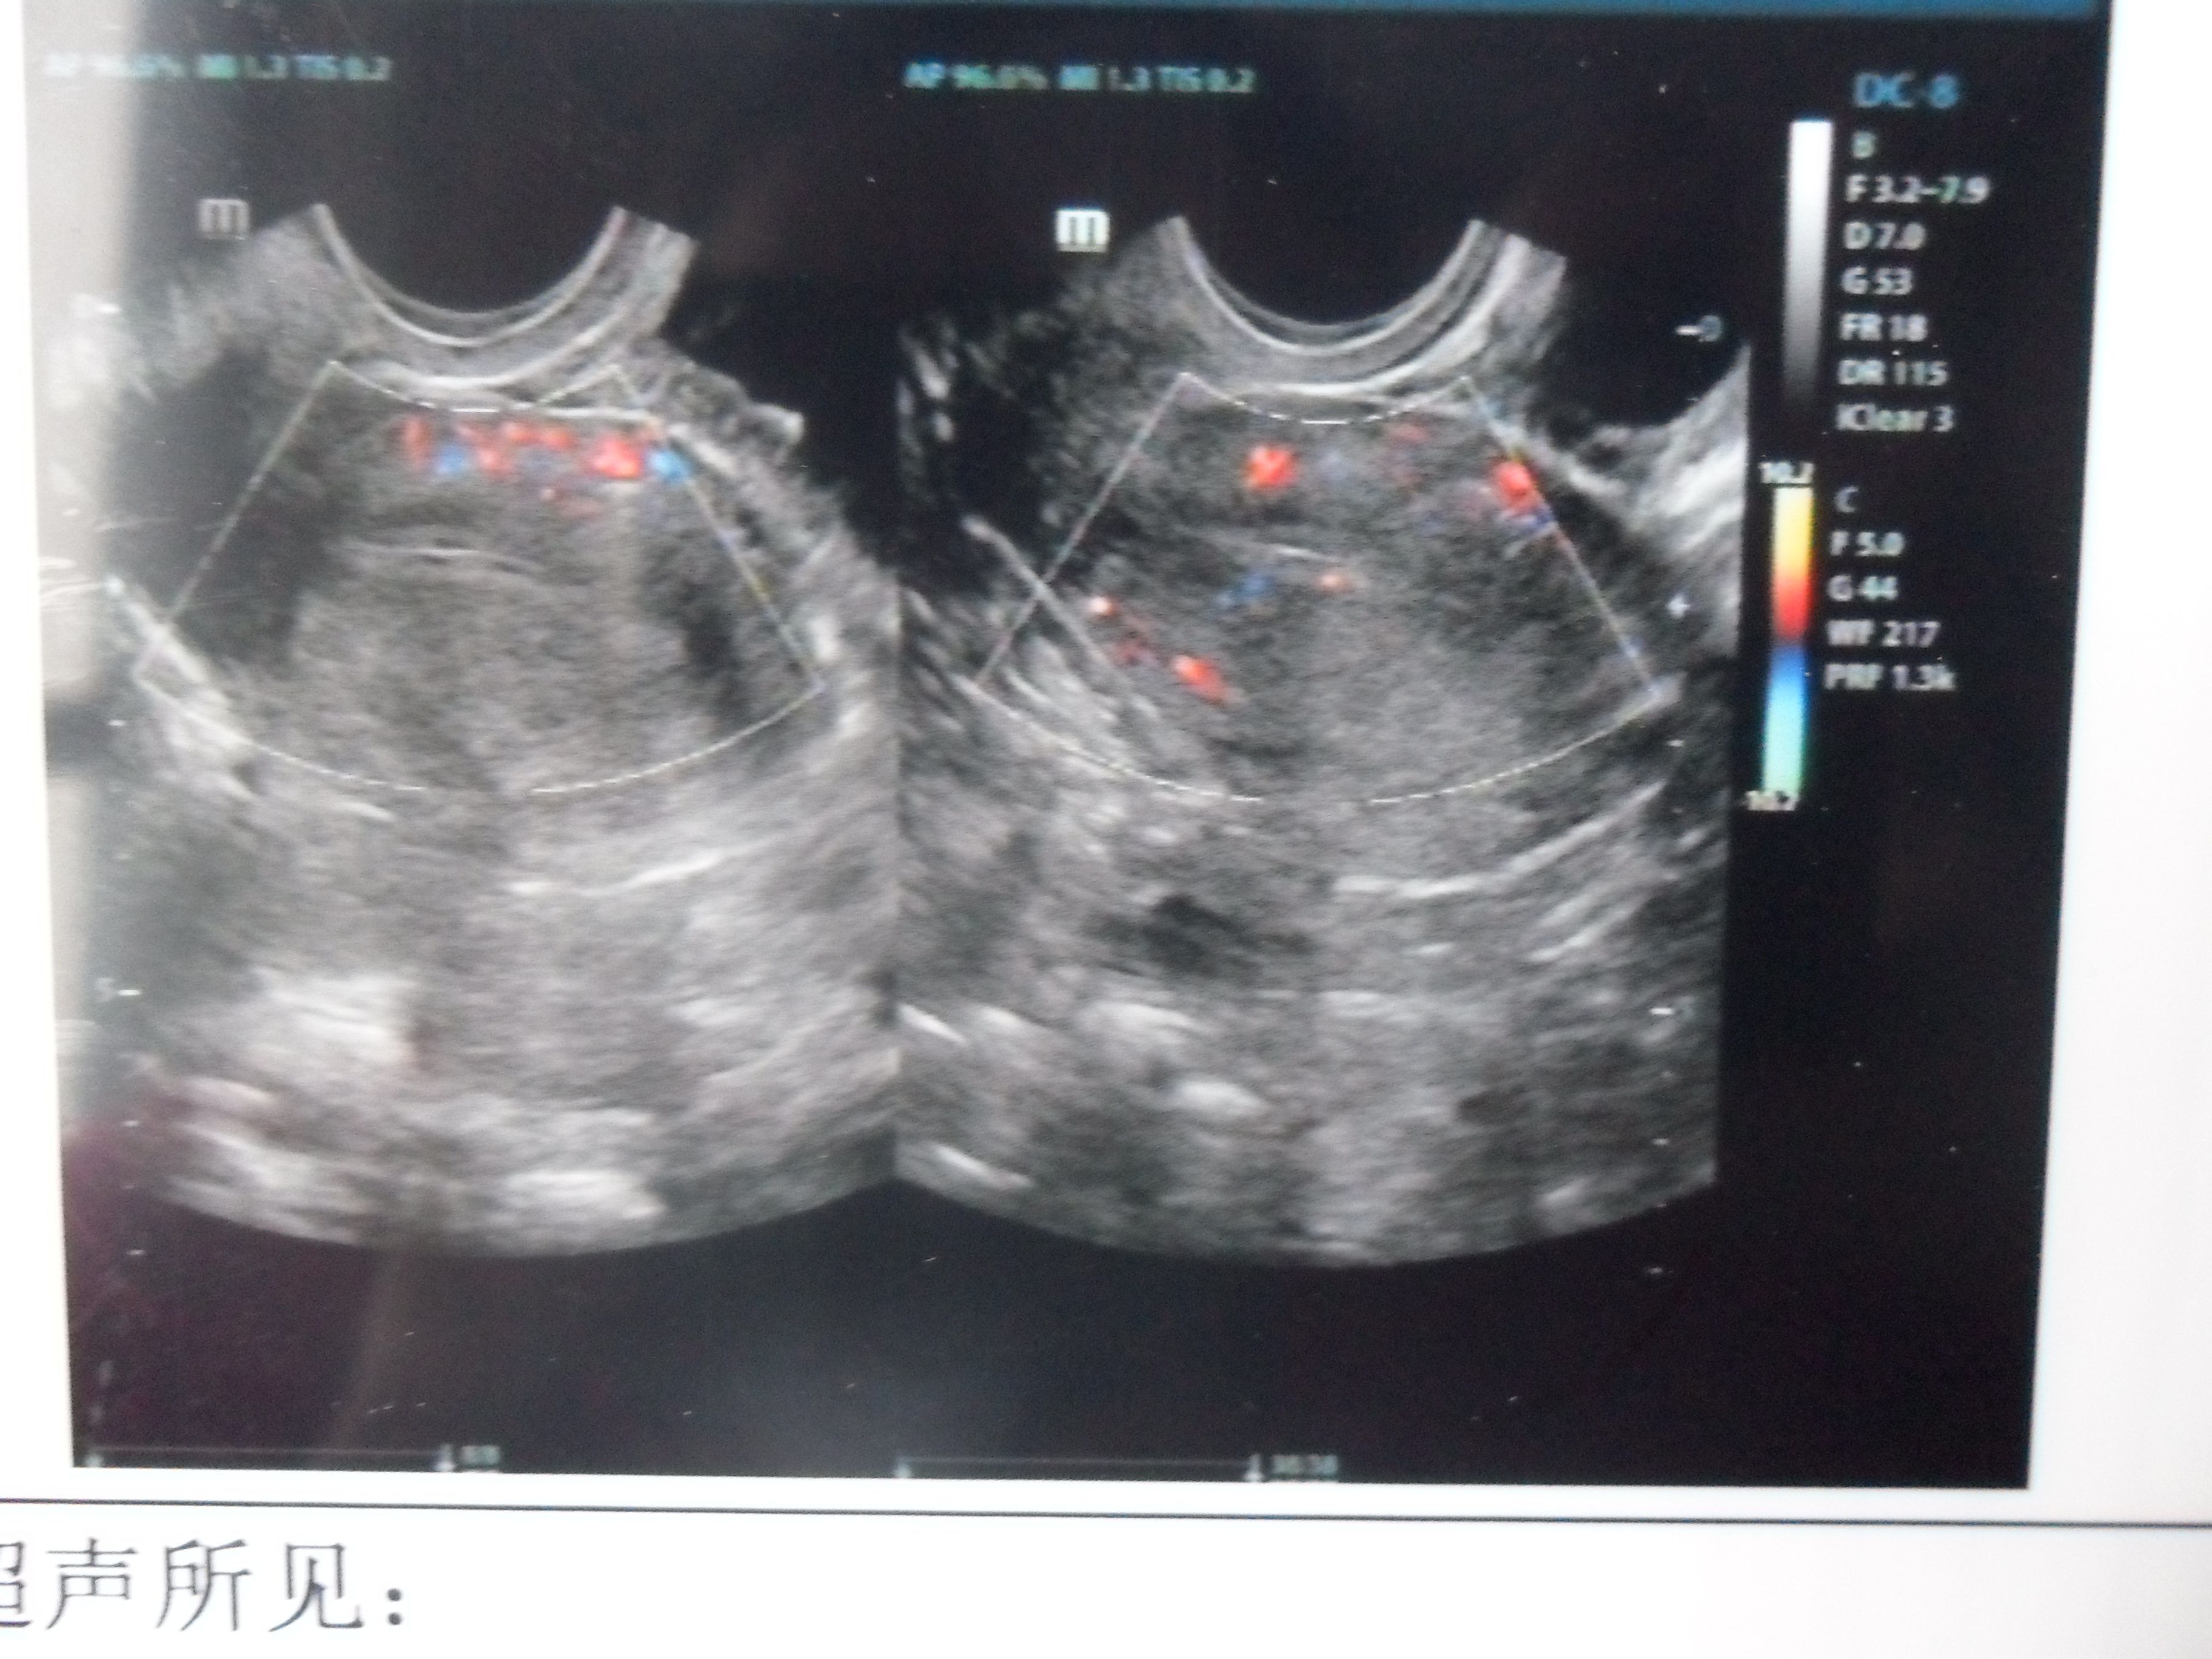

月经不调,其中有一个月没有来月经,月经干净后第二天照了彩超,医生说卵泡数量过多!我想问一下这个 算过多吗?要怎么治疗比较好!以前没有这种状况。未婚 点击展开 匿名用户 2014-02-18 09:25 为您推荐: 其他回答 病情分析: 您这种情况考虑是多囊卵巢, 指导意见: 建议您到专科医院详细检查,明确诊断,对症治疗,不要错过治疗的最佳时间. 进访梦_Jtdf 2014-02-18 09:54 相关问题 我的月经是6月6号,月经一个星期干净,我想知道什么时候是排卵期?平时月经不调 现在在调理!医生说我 我月经不调,然后去妇幼保健院检查出来左侧卵巢多囊 医生开的药吃完了月经也来了 可是现在医生说担心我 我是月经不调的,然后准备想怀孕的,去医院医生开了妇科再造胶囊,吃了一个星期,阴道有点痒还有排一些红